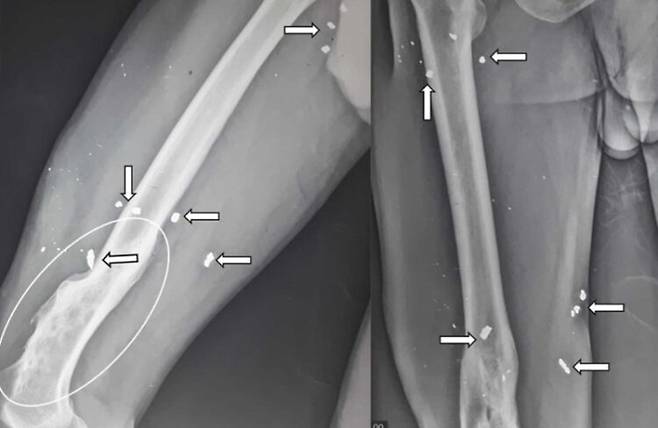

진찰 결과, 오른쪽 허벅지 앞쪽에 누르면 통증이 있는 덩어리가 만져졌고, 고관절과 무릎 관절의 운동 범위가 감소된 상태였다. 사진을 찍어 보니 오른쪽 허벅지에 다양한 크기의 금속 파편 여러 개가 박혀 있는 게 보였다. 허벅지 앞쪽에는 농양도 발생한 상태였다. 농양을 빼내고 실시한 고름 배양 검사에서는 메티실린 내성 황색포도상구균(메티실린 계열 항생제가 듣지 않도록 내성이 생긴 균)이 검출됐다.

의료진은 내성균 감염 치료에 쓰이는 약을 투여하고, 파편을 제거하는 수술을 시행했다. 하지만 모든 파편을 제거하지는 못했다. 6주간의 항생제 치료와 외래 진료 후 남성은 퇴원했다.